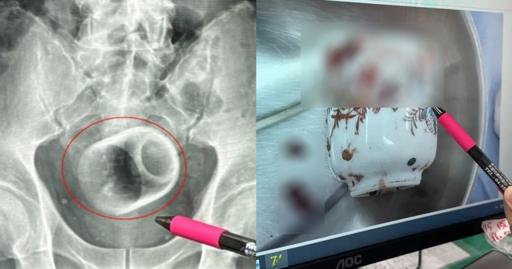

A doctor at the hospital pointed out that while inserting foreign objects into the bottom was not unheard of, they can cause immense damage to internal organs and be fatal.

Things sometimes don’t come out due to shape or they lodge at a weird angle. This increases risk of bowel or rectal perforation as the body tries to push against an obstruction. Think opening a door but a desk is up against it. The cup can also break so now you’ll have ouchie shards that can cut the bowel and create perforations or spill stool into the abdomen. Oh, and cause bleeding.